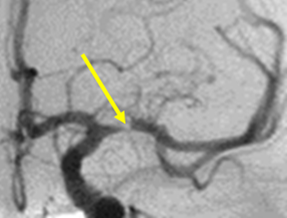

1. หลอดเลือดในสมองตีบ (Atherosclerosis) เกิดจากลิ่มเลือดก่อตัวขึ้นจากผนังหลอดเลือดสมองสมองที่มีคราบไขมันเกาะจนแข็ง ทำให้หลอดเลือดสมองตีบแคบลงจนอุดตัน ปัจจัยเสี่ยงที่สำคัญ ได้แก่ อายุ ความดันโลหิตสูง เบาหวาน ไขมันในโลหิตสูง สูบบุหรี่ แอลกอฮอล์ หรือโรคที่ส่งผลต่อการเปลี่ยนแปลงภายในหลอดเลือด โรคอ้วน เพราะคนอ้วนจะสัมพันธ์กับการนอนกรนหรือภาวะหยุดหายใจขณะหลับ ทำให้มีโอกาสเกิดภาวะหลอดเลือดไปเลี้ยงสมองไม่เพียงพอ

2. หลอดเลือดในสมองอุดตัน (embolic) เกิดจากลิ่มเลือดที่ก่อตัวในเส้นเลือดนอกสมอง เช่น ที่หัวใจ ลอยตามกระแสเลือดไปอุดตันที่หลอดเลือดเล็กๆ ในสมอง ปัจจัยเสี่ยงที่สำคัญ ได้แก่ ภาวะหัวใจเต้นผิดจังหวะ โรคของลิ้นหัวใจ กล้ามเนื้อหัวใจขาดเลือด หรือภาวะหัวใจโต สาเหตุอื่นๆ ที่พบในวัยรุ่น เช่น กีฬาหรืออุบัติเหตุที่มีการบิดหรือสะบัดคอแรงๆ อาจทำให้หลอดเลือดที่คอฉีกขาดได้ อาทิ บันจี้จั๊มพ์ หรือกีฬาเอ็กซ์ตรีม ซึ่งพบได้มากขึ้นในคนไข้กลุ่มวัยรุ่น มักมีอาการปวดคอมาก อ่อนแรงครึ่งซีก หรือช่วงน้ำท่วมมีอาสาสมัครช่วยแบกกระสอบที่คอแล้วอ่อนแรงไปซีกหนึ่ง เป็นต้น นอกจากนี้อาการของหลอดเลือดสมองยังมีหลอดเลือดดำอุดตันด้วย เช่น กลุ่มที่รับประทานยาคุมกำเนิดหลังคลอด ซึ่งจะมาด้วยอาการชักคล้ายหลอดเลือดแดงอุดตัน